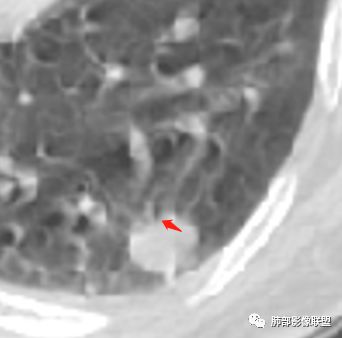

病例1为胸膜下实性小结节,血管脐凹样出入,可见支气管阻塞。病灶膨隆,部分边缘平直,周围晕征不明显,未见分叶,但可见毛刺及胸膜牵拉,增强后明显强化,老年男性,怀疑新生物尤其是腺癌是有理由的。